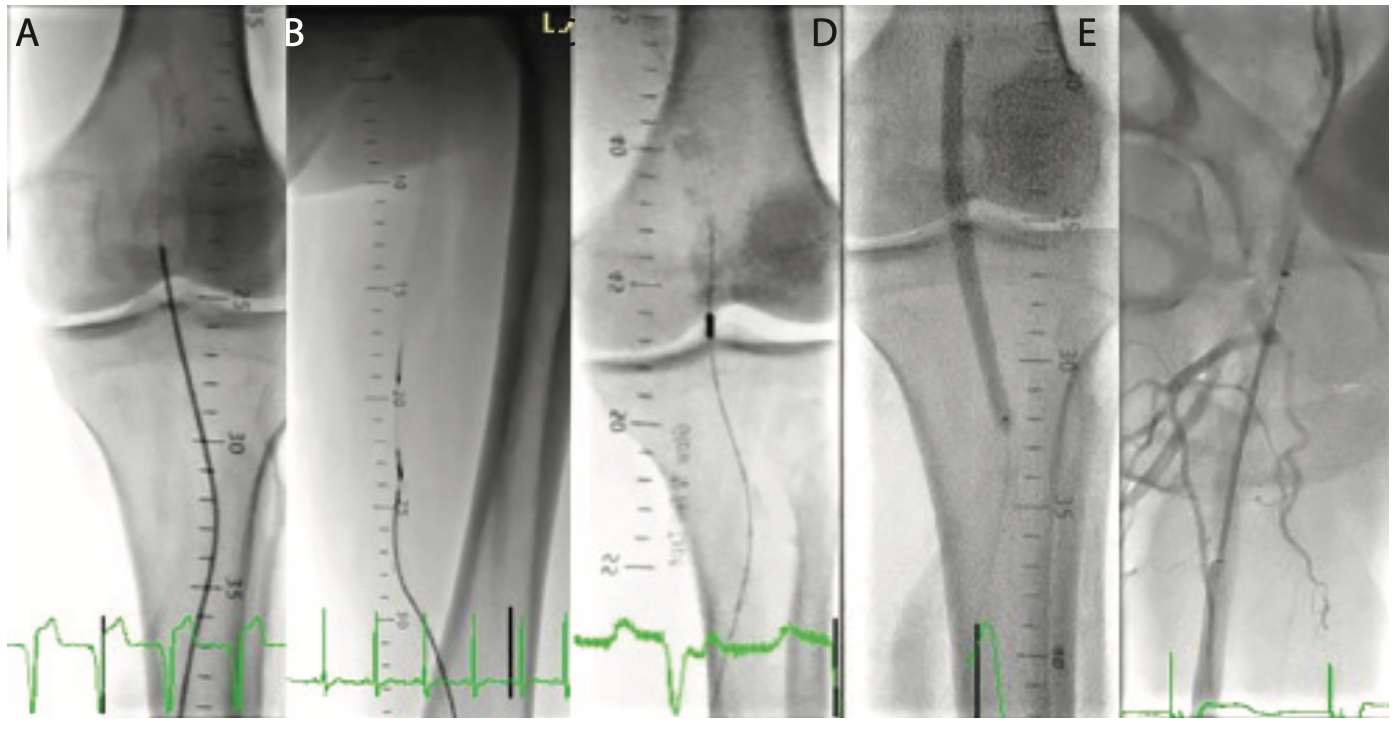

Method for performing procedure. Baseline arterial pressure was recorded through the sheath (Figure 2). Arterial angiography of the outflow circulation was performed using 50:50 diluted contrast and digital subtraction angiography (DSA) (Figure 3A). Guided by the angiography or image-overlay technique, a 0.014˝ workhorse wire, 0.018˝ V18 control wire (Boston Scientific), or 0.035˝ hydrophilic angled Glidewire (Terumo) was advanced through the sheath along with either a 0.018˝ or 0.035˝ Quick-Cross support catheter (Spectranetics) in retrograde fashion. Retrograde angiography of the popliteal artery and superficial femoral artery (SFA) was performed using the Quick-Cross in the popliteal artery (Figures 3B and 3C). Based on the anatomy and the nature of the lesion, either an 0.014˝ wire, 0.018˝ wire, chronic total occlusion (CTO) wire, or CTO crossing device were used at the operator’s discretion to cross the lesions in the popliteal/SFA/or common femoral artery (CFA) distributions. A crossing catheter was advanced over the wire retrograde through the crossed lesion into the CFA and/or iliac artery, and angiography was performed (Figures 3D and 3E). Proximal iliac artery or aortic pressures were recorded. When unable to cross through the occluded artery, or whenever antegrade angiography of the inflow was required, a secondary access was obtained. Left radial artery was chosen whenever possible or convenient; alternatively, the contralateral CFA was used (Figure 4). Irrespective of access choice, contemporary occlusion crossing strategies, including subintimal technique10,11 and SAFARI technique12 were used. Guided by the angiography and radiopaque ruler, disease segments were treated with different treatment modalities at operator’s discretion (Figure 5). Repeat angiography was performed by advancing a 0.035˝ crossing catheter or 4 Fr hydrophilic Glide catheter (Terumo). Between every device exchange, robust flushing of the pedal sheath was performed and pressures were recorded. After the intervention, a final angiography of the entire leg including the outflow was performed using DSA. Final pressure at the TPA from the sheath was recorded (Figure 2).